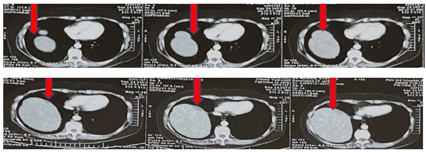

2021年10月8日:汗出,眠差,咳嗽好转,CA125 6.43 U/ml。基因检测:BRCA1/2均为阴性。CT:肝右叶顶部前缘见梭形低密度,无明显强化,约35 mm×14 mm;右侧心膈角多发淋巴结影,肝门及胰头周围多发小淋巴结,大致同前。予原方--生石膏,蜜麻黄,首乌藤,酸枣仁,+珍珠母30 g,麻黄根30 g,28剂,两日一剂,成药同前。

此后患者均规律就诊,规律服药。2022年9月27日复查CT:肝右叶顶部前缘见梭形低密度,无明显强化,约31 mm×13 mm,略缩小;右侧心膈角多发淋巴结影,肝门及胰头周围多发小淋巴结,大致同前;CA125 7.72 U/ml。转归:直至现在,术后5年余,无进展生存4年余,患者无明显不适,复查无明显进展。